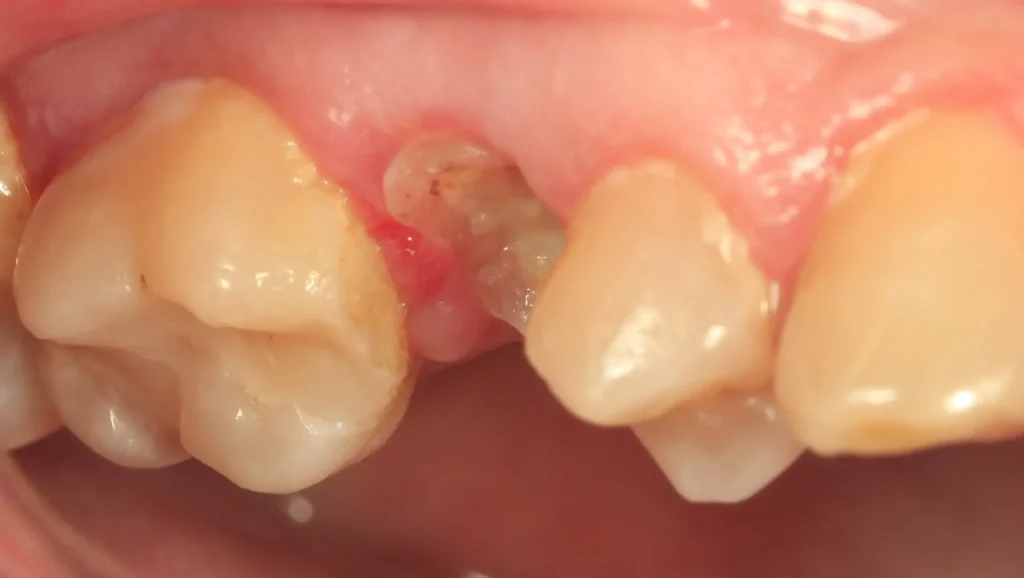

Este caso clínico presenta un diente que inicialmente parecía estar comprometido hasta el punto de necesitar extracción , pero mediante una restauración adecuada se logró darle una segunda vida.

El paciente presentó un diente con una pérdida significativa de estructura dental, probablemente como resultado de caries extensas o trauma. La evaluación inicial apuntaba a que el diente estaba muy dañado para conservarse sin una intervención invasiva, como una extracción. Sin embargo, después de realizar un análisis exhaustivo, se determinó que el diente podía ser restaurado de manera efectiva mediante un tratamiento conservador utilizando una restauración de alta calidad, que preserva la estructura dental original.

Las imágenes del antes y después muestran una notable mejoría en la función y apariencia del diente restaurado. En la imagen previa, se puede observar claramente la destrucción del diente y la posible necesidad de extracción. Sin embargo, en el después, el diente restaurado con disilicato de litio no solo tiene una apariencia natural, sino que también ha recuperado su integridad funcional. Este caso es un excelente ejemplo de cómo, con el tratamiento adecuado y el uso de materiales de alta calidad, es posible evitar la extracción de dientes y ofrecer soluciones que conservan la estructura dental y mejoran la calidad de vida del paciente.